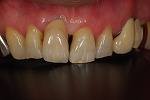

術前

→

術後